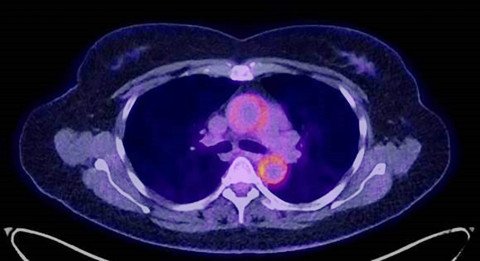

Zudem sind hochauflösende bildgebende Verfahren wie dynamischer Ultraschall, neue MRT-Techniken und Dual-Energy-CT unverzichtbar geworden. Die molekulare Bildgebung mit FDG-PET-CT ermöglicht eine genaue Abklärung gewisser entzündlicher Erkrankungen, etwa bei Vaskulitiden. Mit der Dual-Energy-Röntgenabsorptiometrie und der Analyse der Knochenmikrostruktur (Trabecular Bone Score) optimieren wir die Diagnostik und die Therapie von Osteoporose. Im Jahr 2024 haben wir 1258 Knochendichtemessungen durchgeführt.